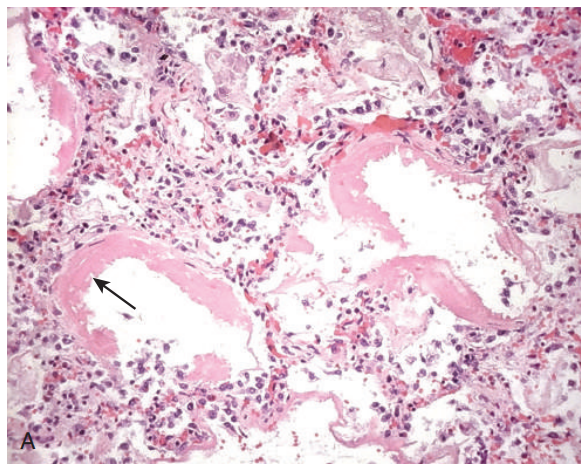

急性期(acute stage):第一周内,以水肿和透明膜形成为特征。

• 毛细血管扩张充血。

• 肺间质和肺泡内水肿伴不等量的红细胞渗出。

• 毛细血管内皮细胞和I型肺泡上皮细胞肿胀和有退行性改变。

• 间质炎细胞浸润。血管内有时见纤维素性血栓。

• 透明膜(hyaline membrane)是一层紧贴肺泡壁的红染均质透明膜样物,含有丰富的胞浆物质、脱落细胞的核碎片及混有少量的纤维素。

beb12279bc933c41ff2fd7ed800ac9ee.png